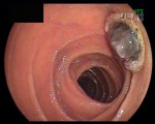

We report on our experience with the Fujinon EN-450 T5 therapeutic double-balloon endoscope (DBE) and compare our findings with the results of earlier capsule endoscopy.

Between August 2005 and July 2009, 150 DBE procedures were conducted in 139 consecutive patients (M/F: 67/72, age: 51.1 years, SD: 18.6 years) who presented at our tertiary referral hospital. The results of previous capsule endoscopy (CE) examinations were available in 27 patients. The indications for DBE included obscure gastrointestinal bleeding (OGIB) in 83 patients, suspected/known IBD in 25, and polyposis/suspected neoplasia in 29 patients. All of the examinations were performed at our outpatient clinic.

In OGIB, abnormal small-bowel findings were noted in 50 patients (60.2%) including angiodysplasias, erosions, and small ulcers. Malignancy was found in 6 patients (7.2%), while an intervention was carried out in 24 patients. In suspected IBD cases, IBD was diagnosed in 5/13 cases. In known IBD patients, assessment of the extent as well as disease behavior and activity was the indication. In polyposis/suspected malignancy, polyps were removed by snare polypectomy in 8 Peutz-Jeghers patients, while primary adenocarcinoma was diagnosed in 4. The concordance of CE and DBE findings was 51.8% (14/27), while in 2 cases DBE provided significantly new information, including 1 malignancy. The average insertion length was app. 213 cm (range: 70-480 cm).